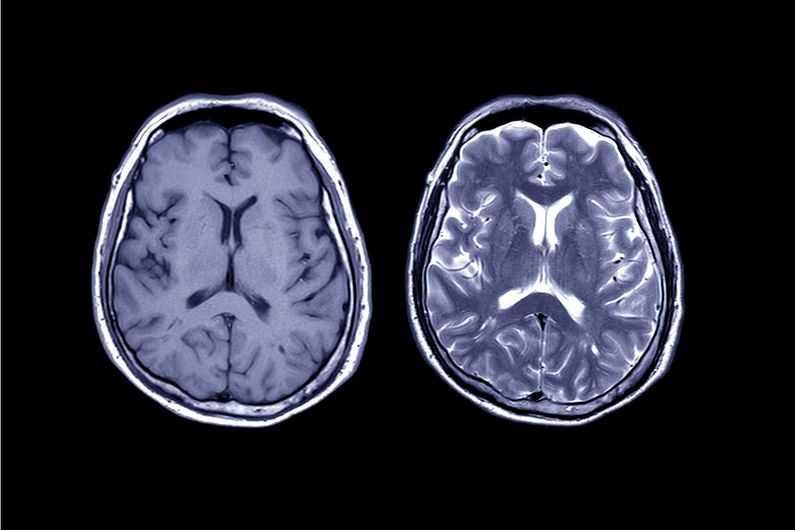

A study shows that Riluzole could be effective in the treatment of certain leukodystrophies, neurodegenerative diseases that attack the myelin in the brain of young children.

Leukodystrophies are rare and almost exclusively genetic diseases characterized by a process of demyelination (damage to the myelin sheath) of the central and peripheral nervous system. The process is primitive in appearance and non-inflammatory and leads to cerebral sclerosis.